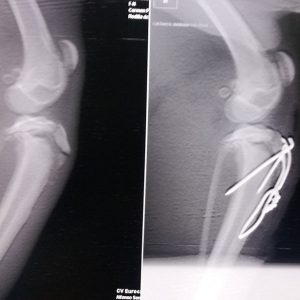

DOMINO es un precioso bodeguero de 7 meses de edad. Es menudo, 38 cm a la cruz y unos 7 kilos de peso. Cuando rescatamos a Domino tenía una lesión en su extremidad trasera, una avulsión de cresta tibial que ya hemos solucionado mediante cirugía.